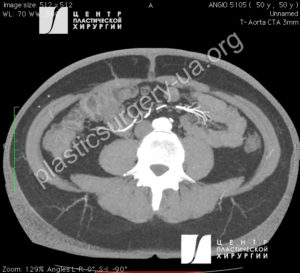

При подготовке к операции с целью определения позиции доминирующего перфорантного сосуда в тканях брюшной стенки применялись ультразвуковой аудио-допплер «Минидоп» с датчиком 8MHz (УЗ-АД) и компьютерная томография (КТ) с ангиографией на мультисрезовом компьютерном томографе Toshiba Aquilion (128 срезов) с использованием контраста «Ультравист». Полученные КТ-ангиограммы обрабатывали в программе ”OsiriX MD” с 3D моделированием для пространственного определения позиции перфорантов в мягких тканях [7,19]. Допплер и КТ-ангиография позволяют нам обнаружить функционально значимые перфоранты, лоцировать их точное расположение (Рис.2 и 3). Обработка полученной КТ-ангиограммы в программе ”OsiriX MD” с 3D моделированием позволяет выделить доминантные перфоранты и определить их позицию в мягких тканях, что значительно облегчает диссекцию интраоперационно (Рис. 4). Динамическая термография зоны формирования лоскута проводилось в комнате с температурой от 20°C до 25°C, с помощью инфракрасной камеры (Dali TE-W2) [2,4]. ). Динамическая термография помогает определить наиболее надежные в плане кровоснабжения зоны планируемого лоскута, функциональное состояние анастомозов между перфорасомами на уровне подкожного сосудистого сплетения. Цифровое фото пациенток до операции, интраоперационно и после операции выполнялось камерой Sony α6000.

Рис. 2. КТ ангиография выполнена с целью предоперационного планирования реконструкции МЖ перфорантным DIEP лоскутом. Сагитальный срез (слева),

Рис. 3. КТ ангиография выполнена с целью предоперационного планирования реконструкции МЖ перфорантным DIEP лоскутом. Поперечный срез (справа). На обеих снимках визуализируются функционально значимые параумбиликальные перфоранты.